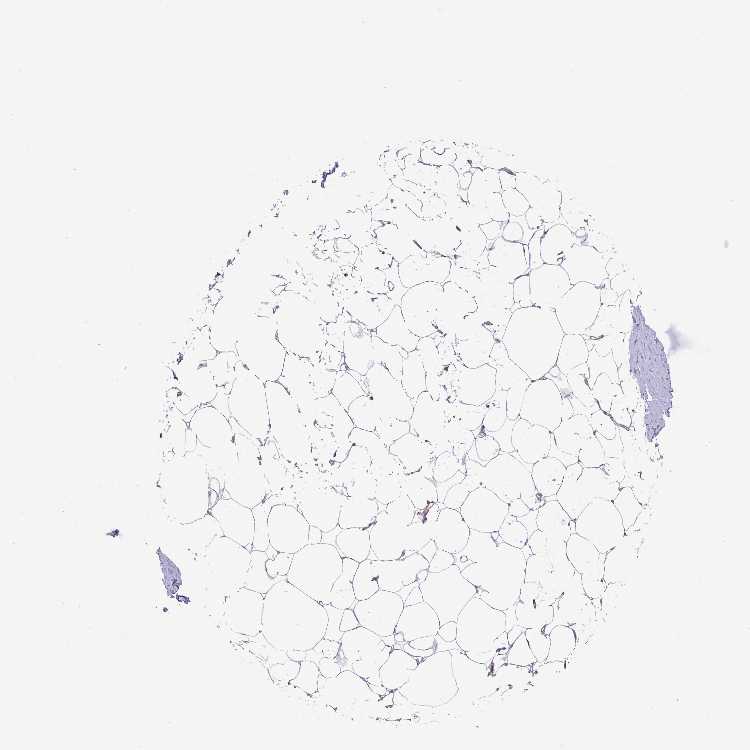

BREAST - Antibody stainingi

Antibody staining in the annotated cell types in the current human tissue is reported as not detected, low, medium, or high, based on conventional immunohistochemistry profiling in selected tissues. This score is based on the combination of the staining intensity and fraction of stained cells.

Each image is clickable and will lead to virtual microscopy that enables deeper exploration of all samples and also displays staining intensity scores, fraction scores and subcellular localization as well as patient and tissue information for each sample.

Antibody HPA051077

Adipocytes Not detected

Glandular cells Medium

Myoepithelial cells Medium